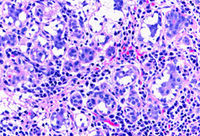

Aspirated material: a group of benign apocrine cells associated with acute and chronic inflammation in keeping with a breast abscess (ThinPrep stain)

From the collection of Liron Pantanowitz, MD, Tufts University School of Medicine, MA